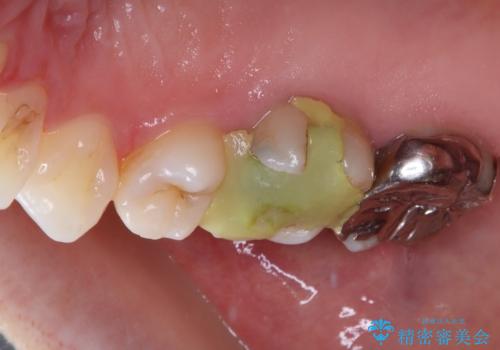

- 奥歯の金属の詰め物が取れたとのことで来院された患者様です。中学生の頃に根管治療を行い、そのあと金属の詰め物をいれていたそうです。

中学生のころに根管治療をしてから特に症状がなく、レントゲンでも病変を認めないため患者様と相談し、再度根管治療は行っていません。

拡大鏡視野下で虫歯の除去を行い、オールセラミッククラウンに適した形に整えました。